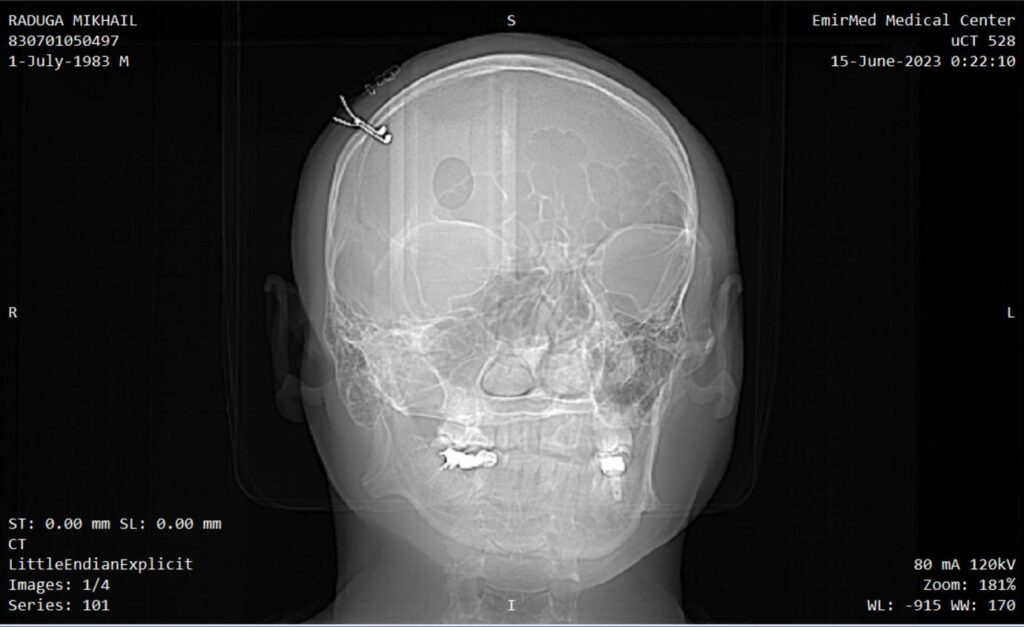

Implant

Device for electrical stimulation

Biocompatibility testing

Photos of computed tomography

Videos of computed tomography